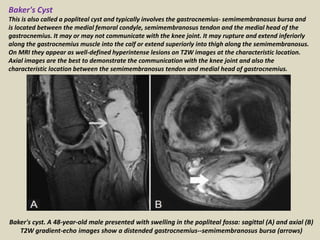

Baker's Cyst

This is also called a popliteal cyst and typically involves the gastrocnemius- semimembranosus bursa and

is located between the medial femoral condyle, semimembranosus tendon and the medial head of the

gastrocnemius. It may or may not communicate with the knee joint. It may rupture and extend inferiorly

along the gastrocnemius muscle into the calf or extend superiorly into thigh along the semimembranosus.

On MRI they appear as well-defined hyperintense lesions on T2W images at the characteristic location.

Axial images are the best to demonstrate the communication with the knee joint and also the

characteristic location between the semimembranosus tendon and medial head of gastrocnemius.

Baker's cyst. A 48-year-old male presented with swelling in the popliteal fossa: sagittal (A) and axial (B)

T2W gradient-echo images show a distended gastrocnemius--semimembranosus bursa (arrows)